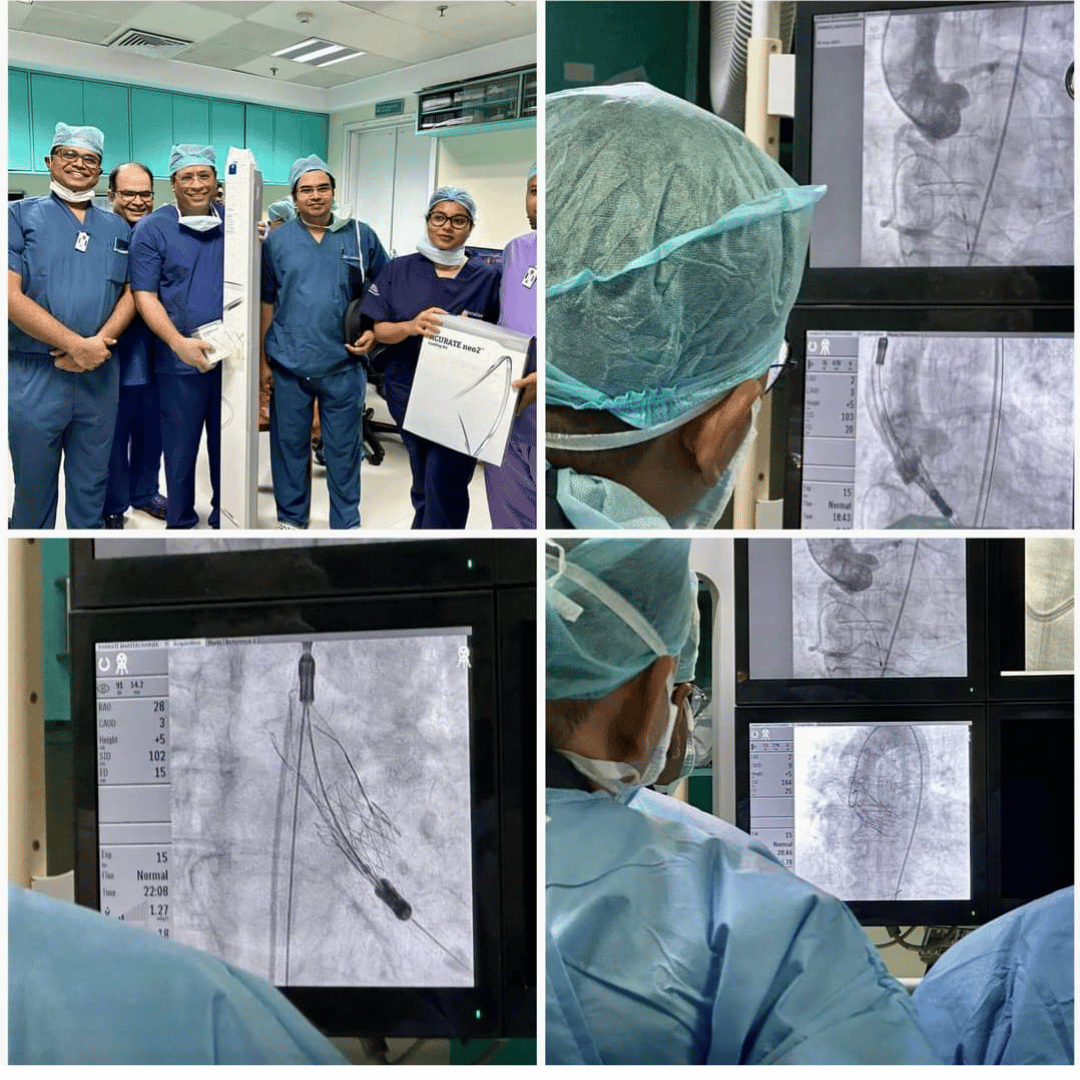

Mentoring young colleagues in their careers is truly rewarding. It was a pleasure to have enthusiastic young operators at our Medica CSP workshop. Additionally, I thoroughly enjoyed scrubbing with Dr. Mahesh at JDWNR Hospital in Thimphu, Bhutan.

CSP workshop at Bankura medical college. It was a great interaction with a highly enthusiastic and skilled team here .